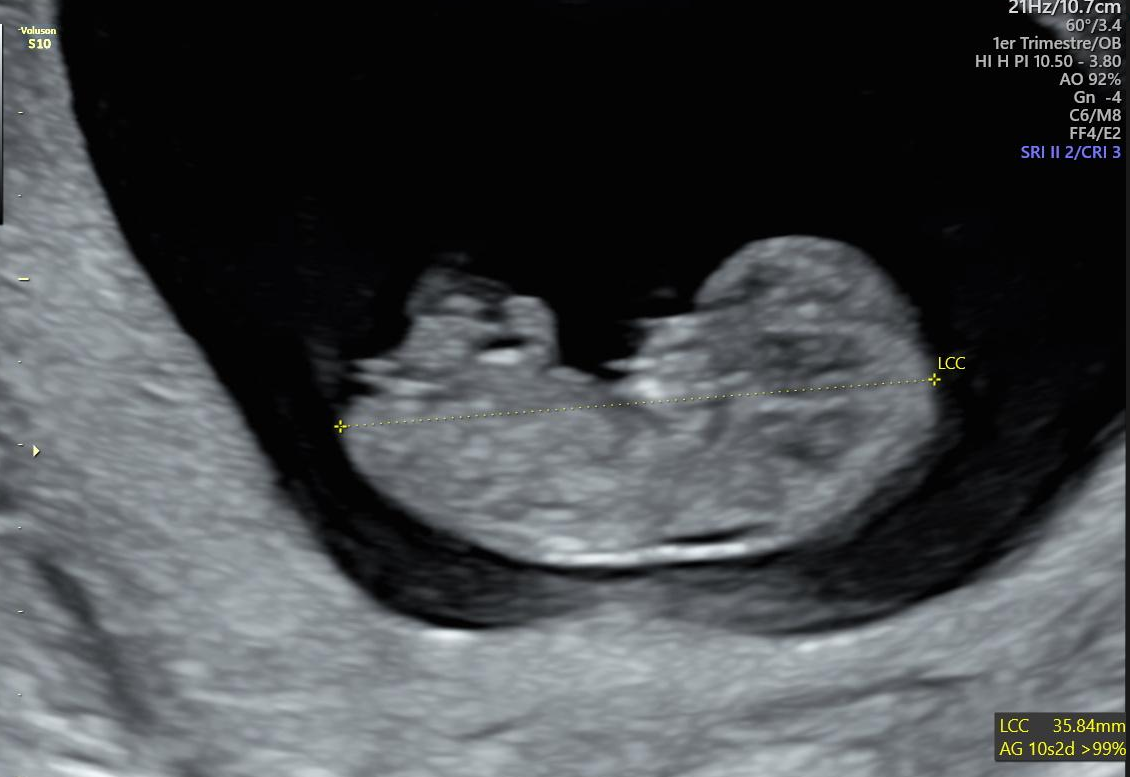

Source: nictukunmi.pages.dev L'échographie de datation le guide complet pour les futurs parents Hello Maman , Qu'est-ce qu'une échographie à 7 sa + 4 jours ? L'échographie à 7 sa + 4 jours est un examen médical couramment pratiqué au cours des premières semaines de la grossesse. Elle permet aux médecins de surveiller le développement de l'embryon et de diagnostiquer des anomalies morphologiques et chromosomiques

Source: bemzenaho.pages.dev Échographie de datation l’essentiel à savoir sur cet examen , Qu'est-ce qu'une échographie à 7 sa + 4 jours ? L'échographie à 7 sa + 4 jours est un examen médical couramment pratiqué au cours des premières semaines de la grossesse. C'est le premier contact visuel que vous avez avec bébé.C'est un moment inoubliable pour vous comme pour le deuxième parent.

Source: bapuecqtb.pages.dev Besoin d avis écho à 7sa Echographie connaître le sexe de votre bébé FORUM Grossesse , En réalité, l'échographie du premier trimestre se fait entre 11 et 13,5 semaines d'aménorrhée tandis que l'échographie de datation a. Elle permet aux médecins de surveiller le développement de l'embryon et de diagnostiquer des anomalies morphologiques et chromosomiques

Source: tswlxhrsu.pages.dev echo a 7sa+4j embryon de 8mm , Elle permet aux médecins de surveiller le développement de l'embryon et de diagnostiquer des anomalies morphologiques et chromosomiques La première phase du cycle (du 1er jour des règles à l'ovulation) est de durée variable, contrairement la 2ème phase (de l'ovulation au 1er jour des règles suivantes), d'une durée fixe de 14 jours